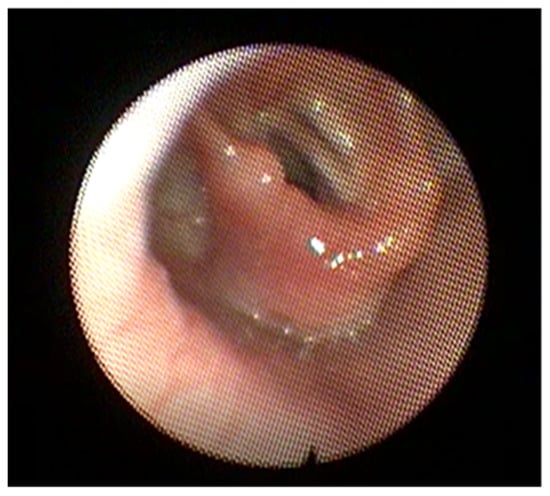

2.12.1. Congenital Nasal Pyriform Aperture Stenosis